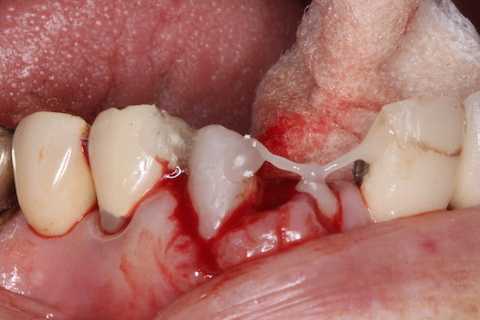

あとは接着固定しながら、歯冠を再建していく。